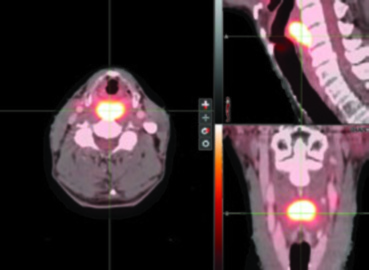

La TC o RM con contraste son esenciales para evaluar compromiso del espacio preepiglótico y paraglótico, extensión laríngea, invasión cartilaginosa macroscópica, extensión a tejidos blandos, invasión esofágica y extensión extracapsular. El PET/TC aporta valor significativo para definir límites tumorales inferiores sutiles — particularmente en el ápice del seno piriforme — y para identificar ganglios hipermetabólicos que pueden escapar a la TC convencional.

La experiencia del Memorial Sloan Kettering Cancer Center ilustra la aplicación práctica de estos volúmenes. En un caso T2N0 de seno piriforme izquierdo, el PET/TC reveló lesión captante extendiéndose hasta la línea media con el margen inferior aproximándose a la región postcricoidea. La RM T1 con gadolinio confirmó desplazamiento del pliegue ariepiglótico izquierdo sin diseminación definitiva a la supraglotis. La planificación con SIB incluyó PTV_6996 (enfermedad macroscópica), PTV_5940 (alto riesgo subclínico) y PTV_5610 (bajo riesgo), con cobertura bilateral de retrofaríngeos y retroestiloides, laringe completa desde hioides hasta cricoides, y niveles IV y VI por la extensión inferior tumoral.